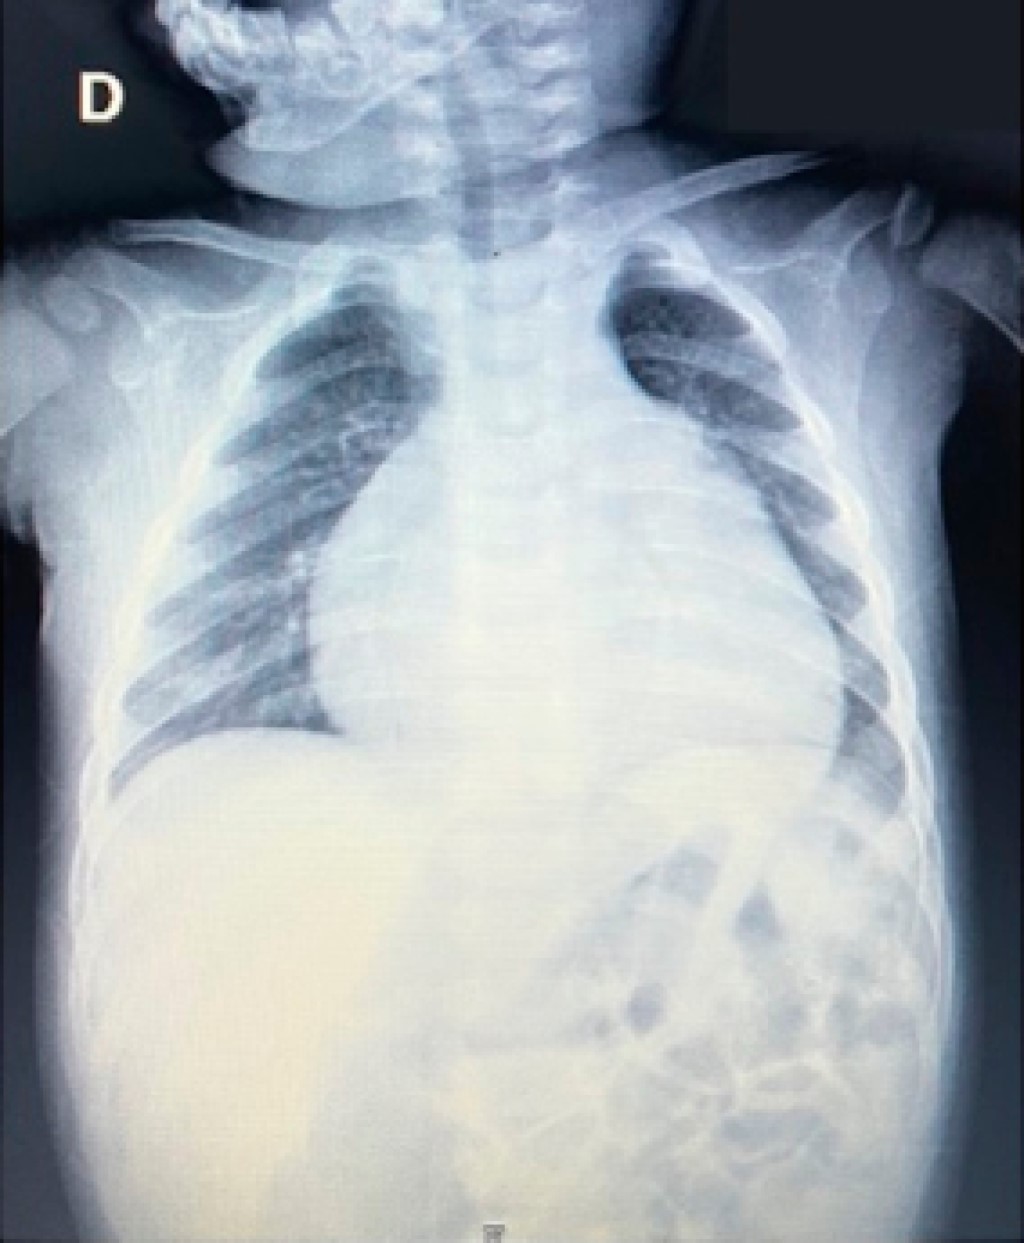

Masculino de un año y cuatro meses sin antecedentes de importancia, ingresó al Departamento de Urgencias por presentar disnea y diaforesis con la alimentación. A la exploración física con oximetría de pulso de 85%. En la radiografía de tórax se observó cardiomegalia a expensas de cavidades derechas con índice cardiotorácico de 0.68 (Figura 1). En el electrocardiograma se encontró ritmo sinusal, con frecuencia cardiaca de 150 latidos por minuto, desviación del eje eléctrico a la derecha con crecimiento de las cavidades derechas.

Figura 1